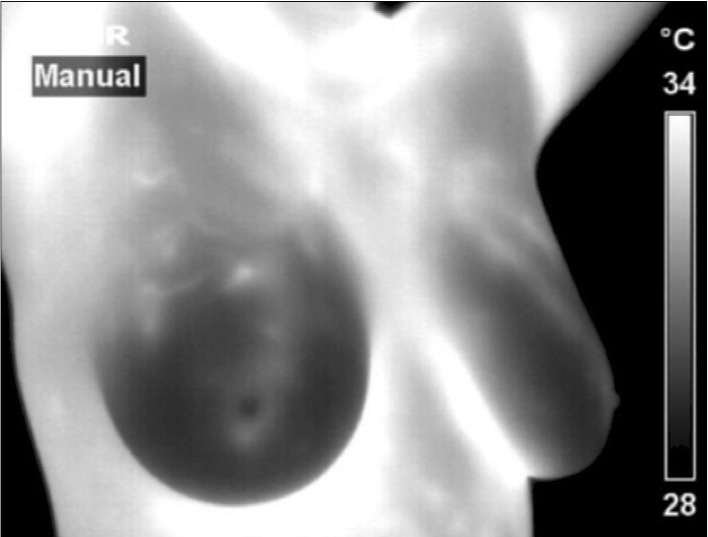

Normal Image  Abnormal Image: Cancer in the left breast

missed by a Mammogram